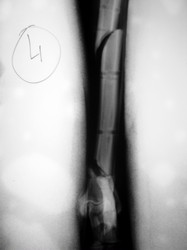

PRÁCTICAS CURSO DE FIJACIÓN EXTERNA PERFECCIONAMIENTO.

Híbrido.